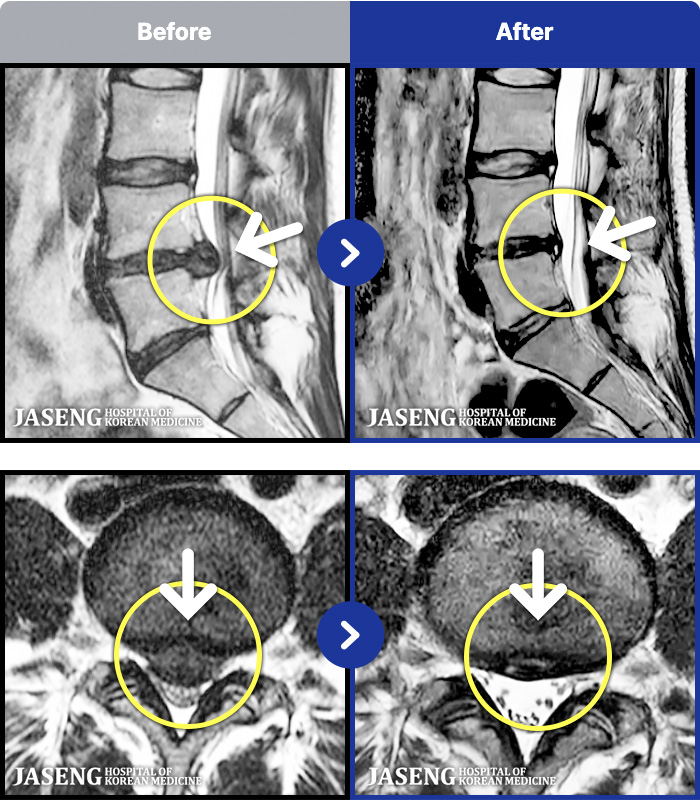

1,286 MRI ũ ʸ Ȯϼ.

[ϻ] 24.07.25~25.08.01